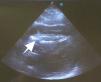

Después de 36h de la intervención la paciente presenta diaforesis; se realiza radiografía de tórax sugiriendo que el electrodo ventricular del cardiodesfibrilador implantable (CDI) se encontraba fuera del corazón (figs. 1 y 2); minutos después la paciente presenta palidez, frialdad generalizada con taquicardia e hipotensión severa; al examen físico se obtiene TA: 64/30mmHg; FC: 120lpm; FR: 30rpm, SatO2: 91%, ruidos cardiacos velados y ecocardiograma el cual muestra colapso ventricular derecho, derrame pericárdico y el electrodo (figs. 3 y 4), por lo que es trasladada inmediatamente a salas de cirugía con la sospecha de taponamiento cardiaco; se realiza esternotomía media evidenciando: hemopericardio aproximadamente 2.000cc, soluciones de continuidad en número de 2 en el ventrículo derecho, la primera puntiforme de 4mm, correspondiendo al electrodo de fijación auricular el cual se movilizó muy probablemente durante el preoperatorio, dado que en la radiografía prequirúrgica se encontraba normoinserto, y otra de 3cm en la pared anterior del ventrículo derecho a través de las cuales emergen los electrodos de fijación activa del dispositivo (fig. 5), con sangrado activo masivo, aurículas, ventrículos y grandes vasos colapsados; se introduce sonda Foley sobre defecto de mayor tamaño con posterior insuflación de la misma controlando parcialmente el sangrado, cardiorrafia y paso de hemoderivados directo al corazón por la sonda; presenta asistolia requiriendo maniobras de reanimación cardiocerebropulmonar avanzadas durante 20min sin obtener respuesta, por lo que la paciente fallece.

El diagnóstico de la perforación ventricular secundaria a electrodos de marcapasos la podemos identificar y confirmar con radiografía de tórax como lo observamos en nuestro caso, en el cual se encontraba el electrodo ventricular fuera de la cámara cardiaca. Otros métodos diagnósticos pueden ser el fluoroscopio, la ecocardiografía o TAC de tórax, encontrándose en esta última alteraciones de hasta el 15% de pacientes asintomáticos durante los controles postimplante del dispositivo10,23,24. En el ecocardiograma tridimensional podemos obtener una mayor precisión que en la TAC de tórax en la identificación de la perforación ventricular por electrodos, debido principalmente al efecto tomográfico conocido como «estrella» causado por los materiales del electrodo (figs. 8 y 9), haciendo difícil el diagnóstico. No existe consenso sobre criterios radiográficos diagnósticos universalmente aceptados entre los grupos de radiólogos, por esto la correlación clínica nos orienta. Todos estos estudios orientan al diagnóstico, pero la no evidencia del electrodo fuera del corazón no nos descarta la complicación, como sucedió en nuestro caso donde hubo una migración del electrodo de fijación activa auricular derecho con posterior perforación del ventrículo ipsilateral, lo cual nos muestra una complicación aún más infrecuente debido a la perforación ventricular por el electrodo ubicado en la aurícula17,25,26.